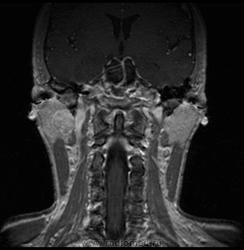

06.06.2011 МРТ - головы и шеи.

Пацентка 36 лет, с жалобами на припухлось в околоушной области справа.

В глубокой доле  правой околоушной железы  на фоне неизмененной паренхимы зона  гетерогенного по Т2, гипоинтенсивного по Т1  с единичными гиперинтенсивными включениями.При контрастировании- накопление контраста диффузное неоднородное и по периферии.Рискну предположить злокачественное образование ( аденокарцинома) с низкой степенью злокачественности( есть капсула, экспансивный рост).Сильно не расстреливайте.

Проблема в том, что перед челюстно-лицевым хирургом стоит распространенность любого объемного процесса, в данном случае все упирается в возмможную травму лицевого нерва и конечно же с дальнейшим его парезом, а ведь женщина  еще молодая. Образование имеет тонкостенную оболочку, по структуре неоднородно, с наличием кальцината, при этом МР-сигнал от окружающих анатомических структур(как костных так и мышечных) не изменен, т.е. об инфильтративном росте речи не идет, в какой то степени доброкачественное. В конкретном случае лицевой нерв с ретромандибулярной веной просто несколько оттеснен.

По гистологии аденома околоушной слюнной железы, но после удаления пока сохраняется парез лицевой мускулатуры, возможно временный.